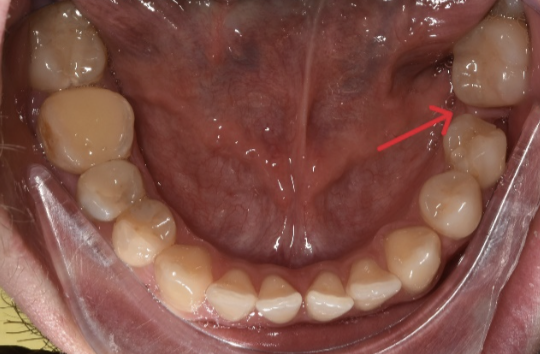

Aici avem un caz in care inghesuirea dentare grava s-a rezolvat prin tratament orthodontic cu extractii dentare.

Se poate observa ca nu exista spatiu pentru eruptia caninilor.

S-a realizat extractia a 2 premolari: